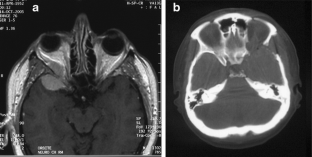

Fig. 1

Fig. 2